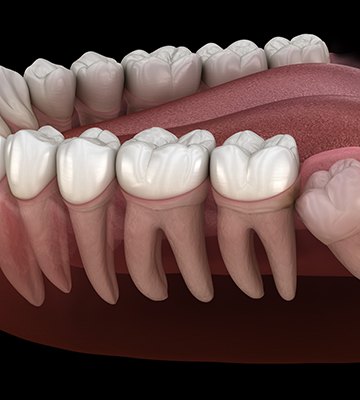

Wisdom teeth, sometimes called third molars, refer to the teeth found at the very back of the mouth, which usually begin to develop and erupt during the teenage years. Most people have four wisdom teeth total, one in every quadrant of their mouth—but in rare cases, some have fewer or more.

Our ancestors relied on their wisdom teeth to bite and chew their food, since their diets were much coarser and consisted of a lot of raw items. However, modern diets are much easier to eat, and humans have evolved smaller mouths over time, which means the wisdom teeth, no longer needed, don’t often have room to properly erupt.